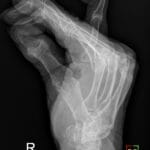

- Radiology Cases: Images with a to-the-point discussion highlighting the specific diagnostic criteria.

Latest Radiology Cases